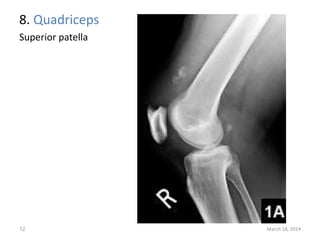

The document lists 10 common sites of avulsion fractures caused by the tearing away of tendons or ligaments from bone. It identifies the specific muscles or tendons that can cause avulsion fractures at the iliac crest, ischial tuberosity, greater trochanter, lesser trochanter, posterior calcaneus, olecranon process, superior patella, inferior patella, and tibial tuberosity.